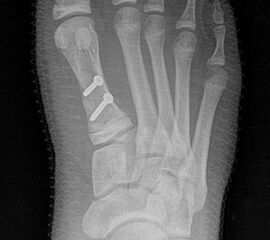

Bezüglich der Operationstechniken wird von früher häufig durchgeführten alleinigen Weich­teileingriffen am Großzehengrundgelenk aufgrund hoher Rezidivraten abgeraten 15. Die Operation nach Mc Bride mit lateralem Release, Exzision des lateralen Sesambeins, Abtragen der Pseudoexostose, Sehnenetransfer des M. adductor hallucis und mediale Kapselraffung zeigte unbefriedigende Mittel- und Langzeitergebnisse 16. Die Cerclage fibreux (mediale Kapselraffung) und das laterale Kapselrelease wird heute in Kombination mit einem knöchernen Eingriff angewendet. Bezüglich des Einsatzes von minimalinvasiven Operations­techniken vor Wachstumsabschluss liegen bisher keine Daten vor. Alle Osteotomien lassen sich nach Bedarf miteinander kombinieren. Es ist darauf zu achten, dass Osteotomien keine offenen Wachstumsfugen verletzen.

• Medial zuklappende Grundphalanxosteotomie nach Akin 17

• Subcapitale distale Chevron Osteotomie nach Austin 18

• Diaphysäre Osteotomie

• Scarf 19

• Ludloff 20

• Proximale Metatarsale I Osteotomien 21

• medial aufklappend – verlängernd

• lateral zuklappend – verkürzend

• bogenförmige Crescentic Osteotomie

• proximale Chevron Osteotomie

• proximale Verschiebeosteotomie

• medial aufklappende Cuneiforme I Osteotomie 1522

• Wachstumslenkung: Hemiepiphysiodese der lateralen Basisfuge am Metatarsale I  23

• Nach Schluss der Wachstumsfugen: TMT I Arthrodese nach Lapidus 2425